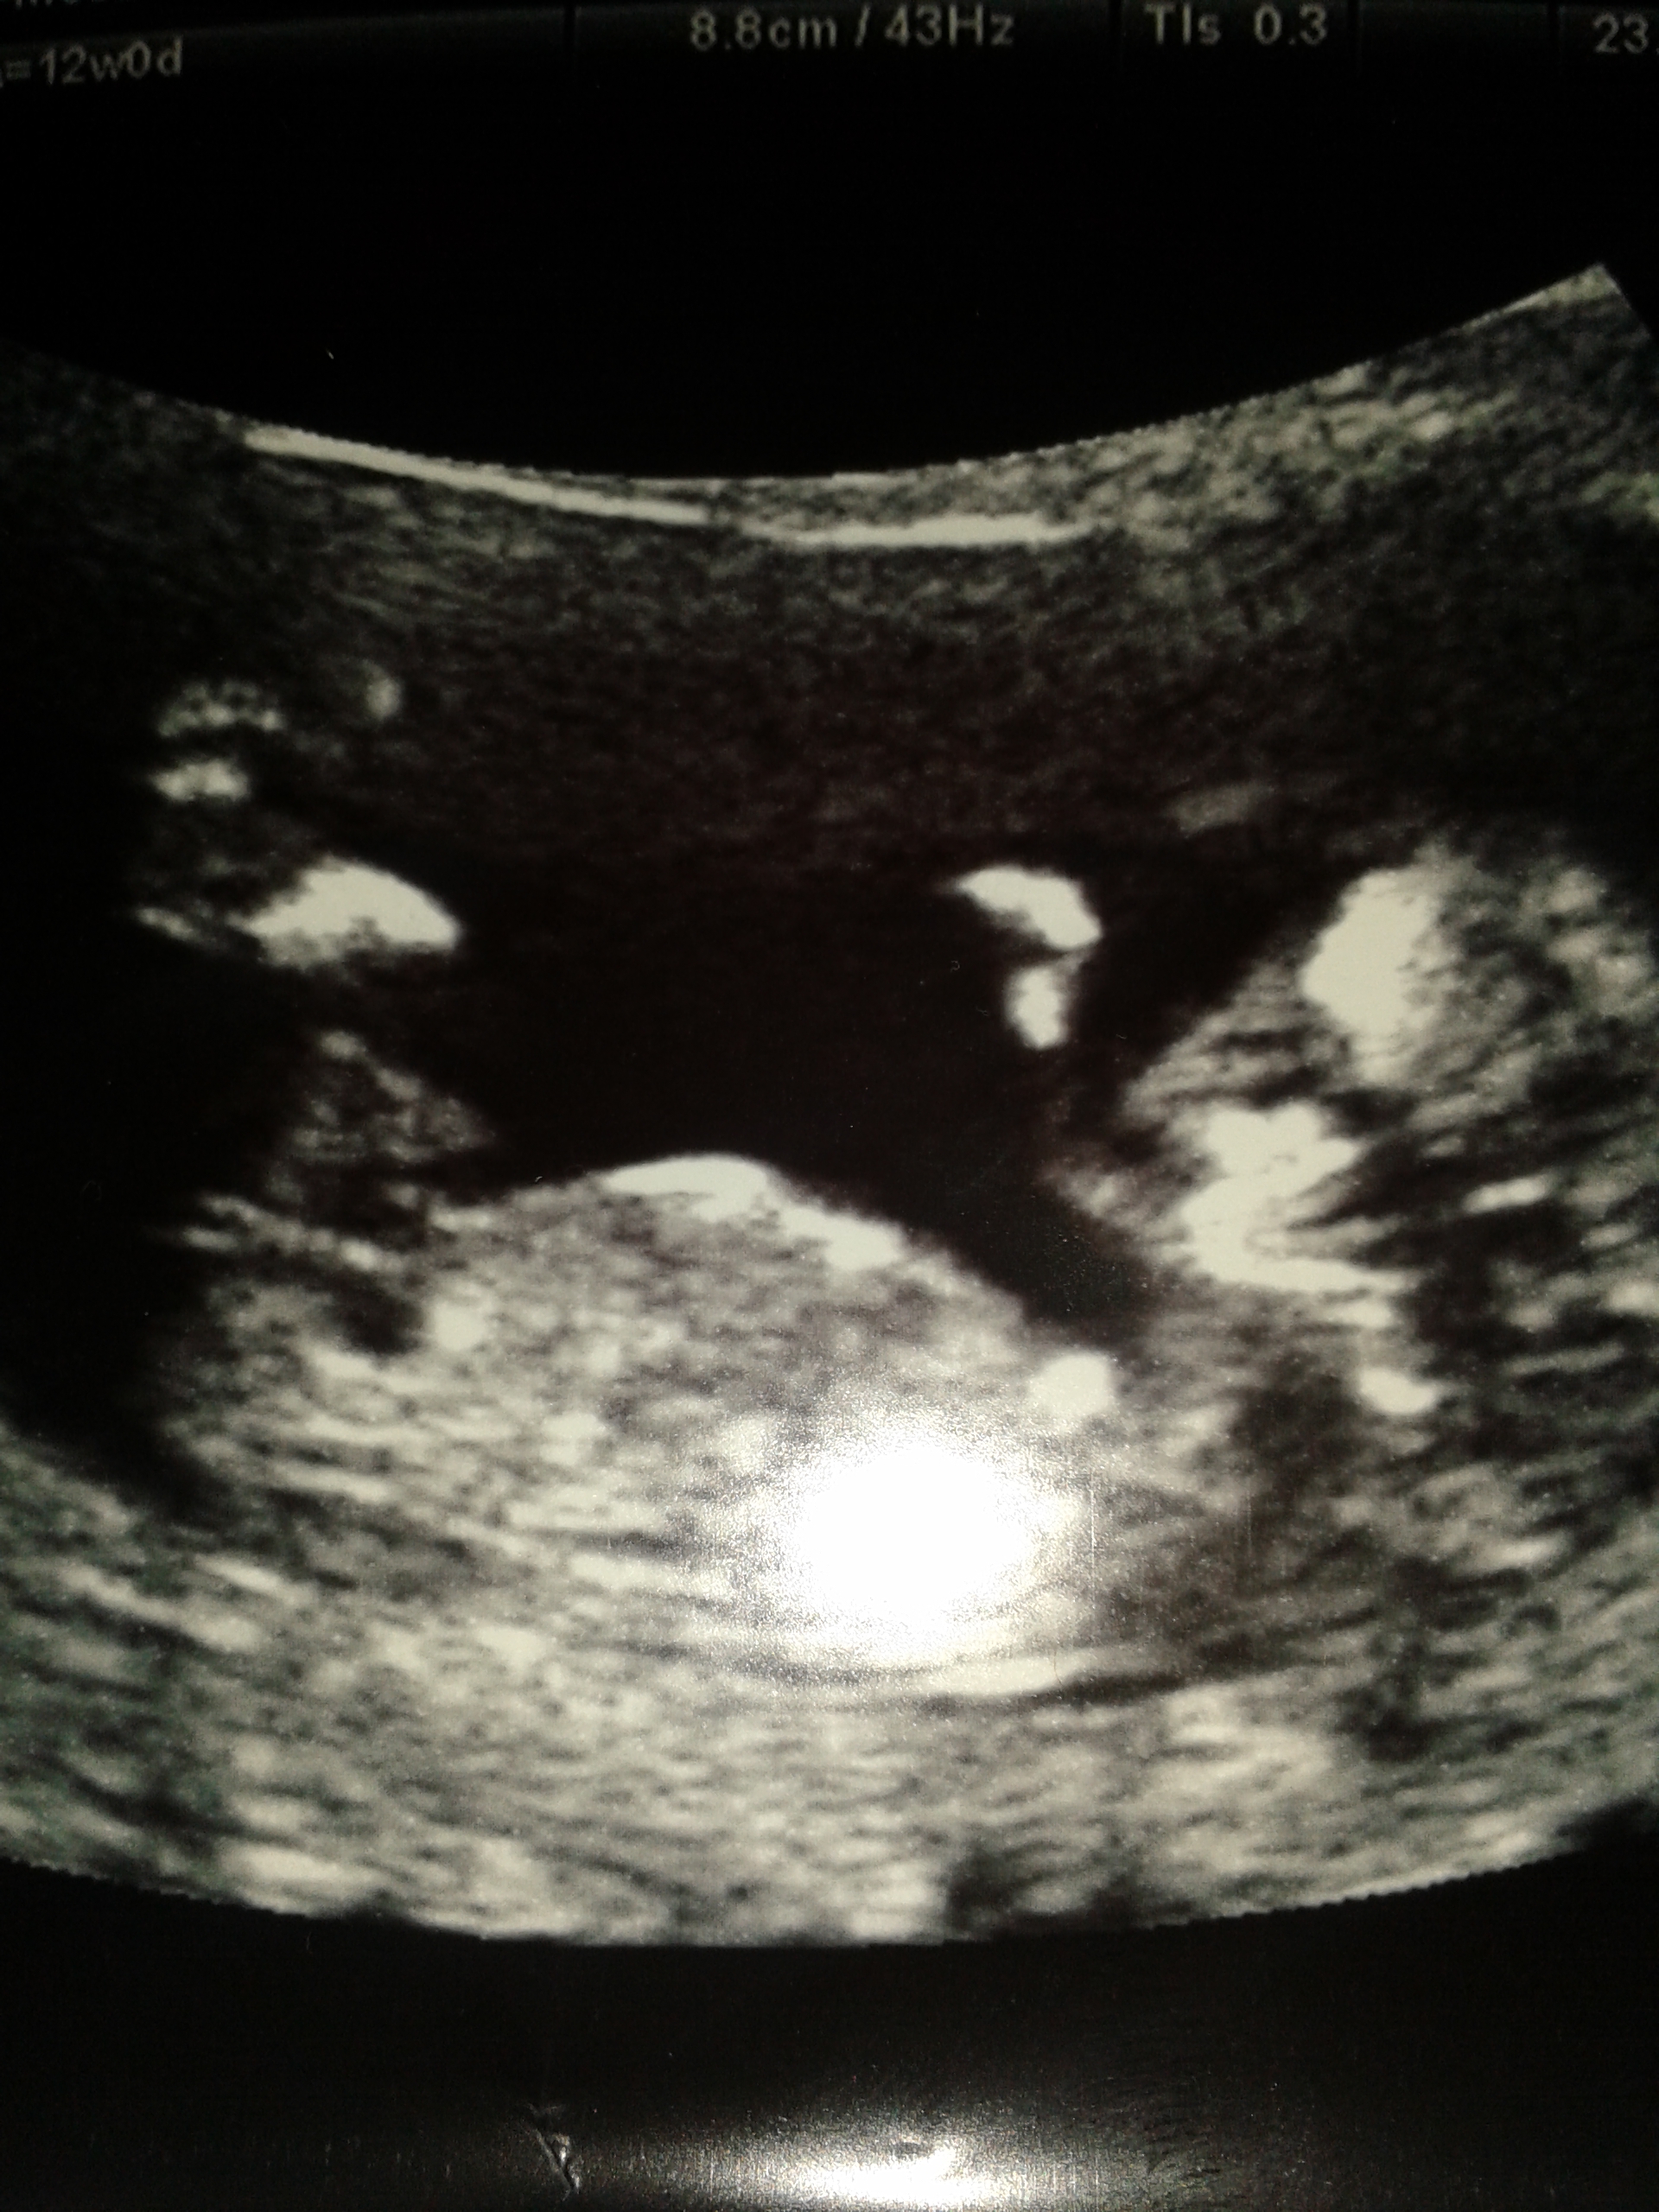

Hi all...i am all new hier and would really really like to know what you think about my u/s picture at 12 weeks...nub experts please give it a shot..Attachment 22694

It looks girly now but being only 12 weeks 0 days, it still has time to rise.

This looks girly to me too - i'm sending you some rising nub dust in exchange for your flat nub which I hope to see next wednesday at my own ultrasound! Good luck!